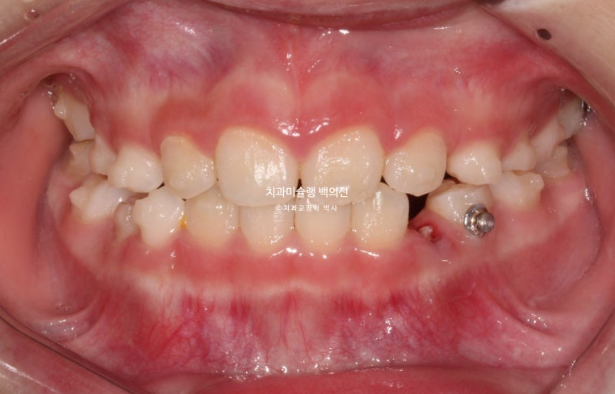

드디어 앞니 4개가 나왔으며 반대교합 치료 결과는 잘 유지되고 있습니다.

어금니 반대교합의 원인은 좁은 상악 악궁에 있습니다.

이제 인비절라인퍼스트 치료로 악궁확장, 앞니배열 등을 먼저 진행하여 교합간섭 해소를 도모합니다.

23년 6월부터 11월까지, 6개월간 첫세트 30개 장치를 모두 낀 후 모습입니다.

악궁확장을 통해 어금니 반대교합은 해소되었고 앞니배열은 좋아졌습니다.

나중에 영구치 송곳니 날 공간도 충분히 마련되었습니다.